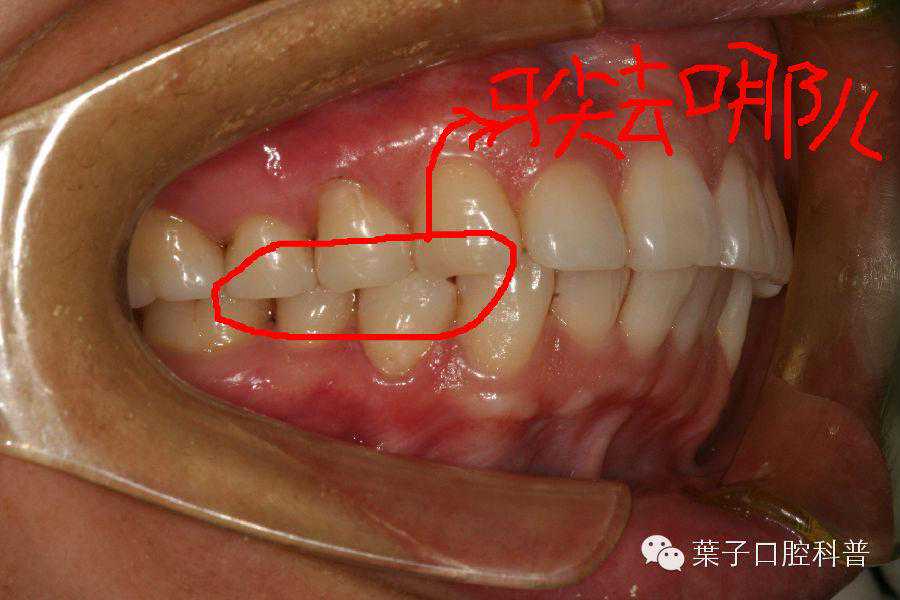

牙齿长得好与坏跟这个人的脸型好看与否常常有着不可分割的关系,各位先看看几张不同面型与咬合的图片:

从这几幅图可以看出,突脸型的人的牙齿多数情况也是向外突的,而直面型的牙齿往往也比较直立,凹面型的人几乎不用张开嘴也能猜到他八九不离十是地包天。